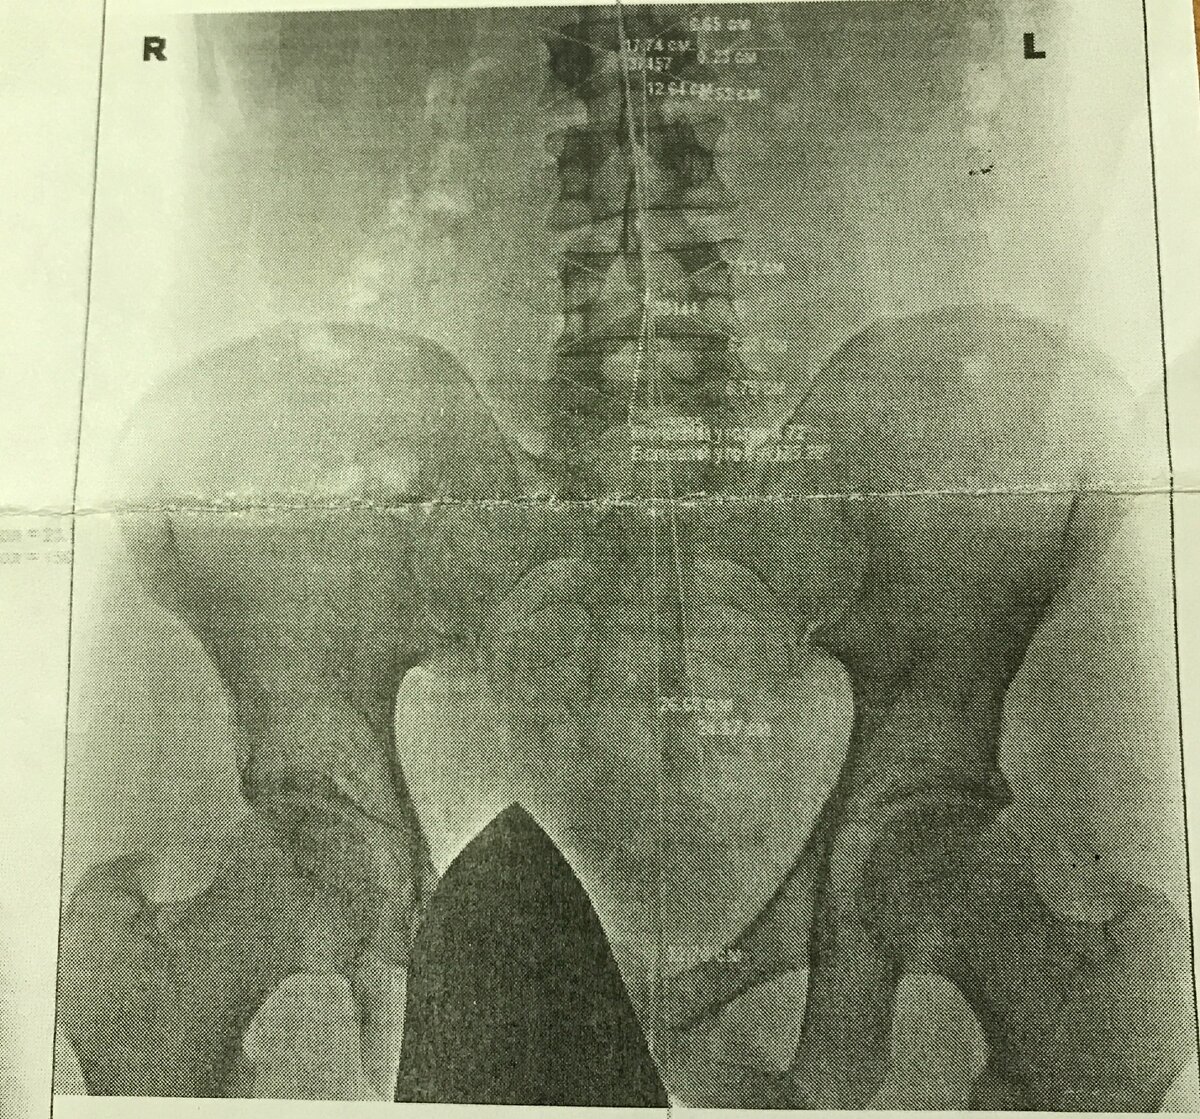

После этого разговора мне стало не по себе, мне показалось, что моя нога стала болеть ещё сильнее и я решил тоже обратиться к врачу. Наверное, я очень мнительный. Врач отправил меня на рентген, где никаких серьёзных проблем обнаружено не было. Рентгенолог сказал мне, что на снимке есть только нарушение осанки и начальные признаки остеохондроза поясничного сустава и посоветовал заняться физкультурой. Врач, который отправил меня на рентген, посоветовала заняться йогой и делать зарядку по утрам.